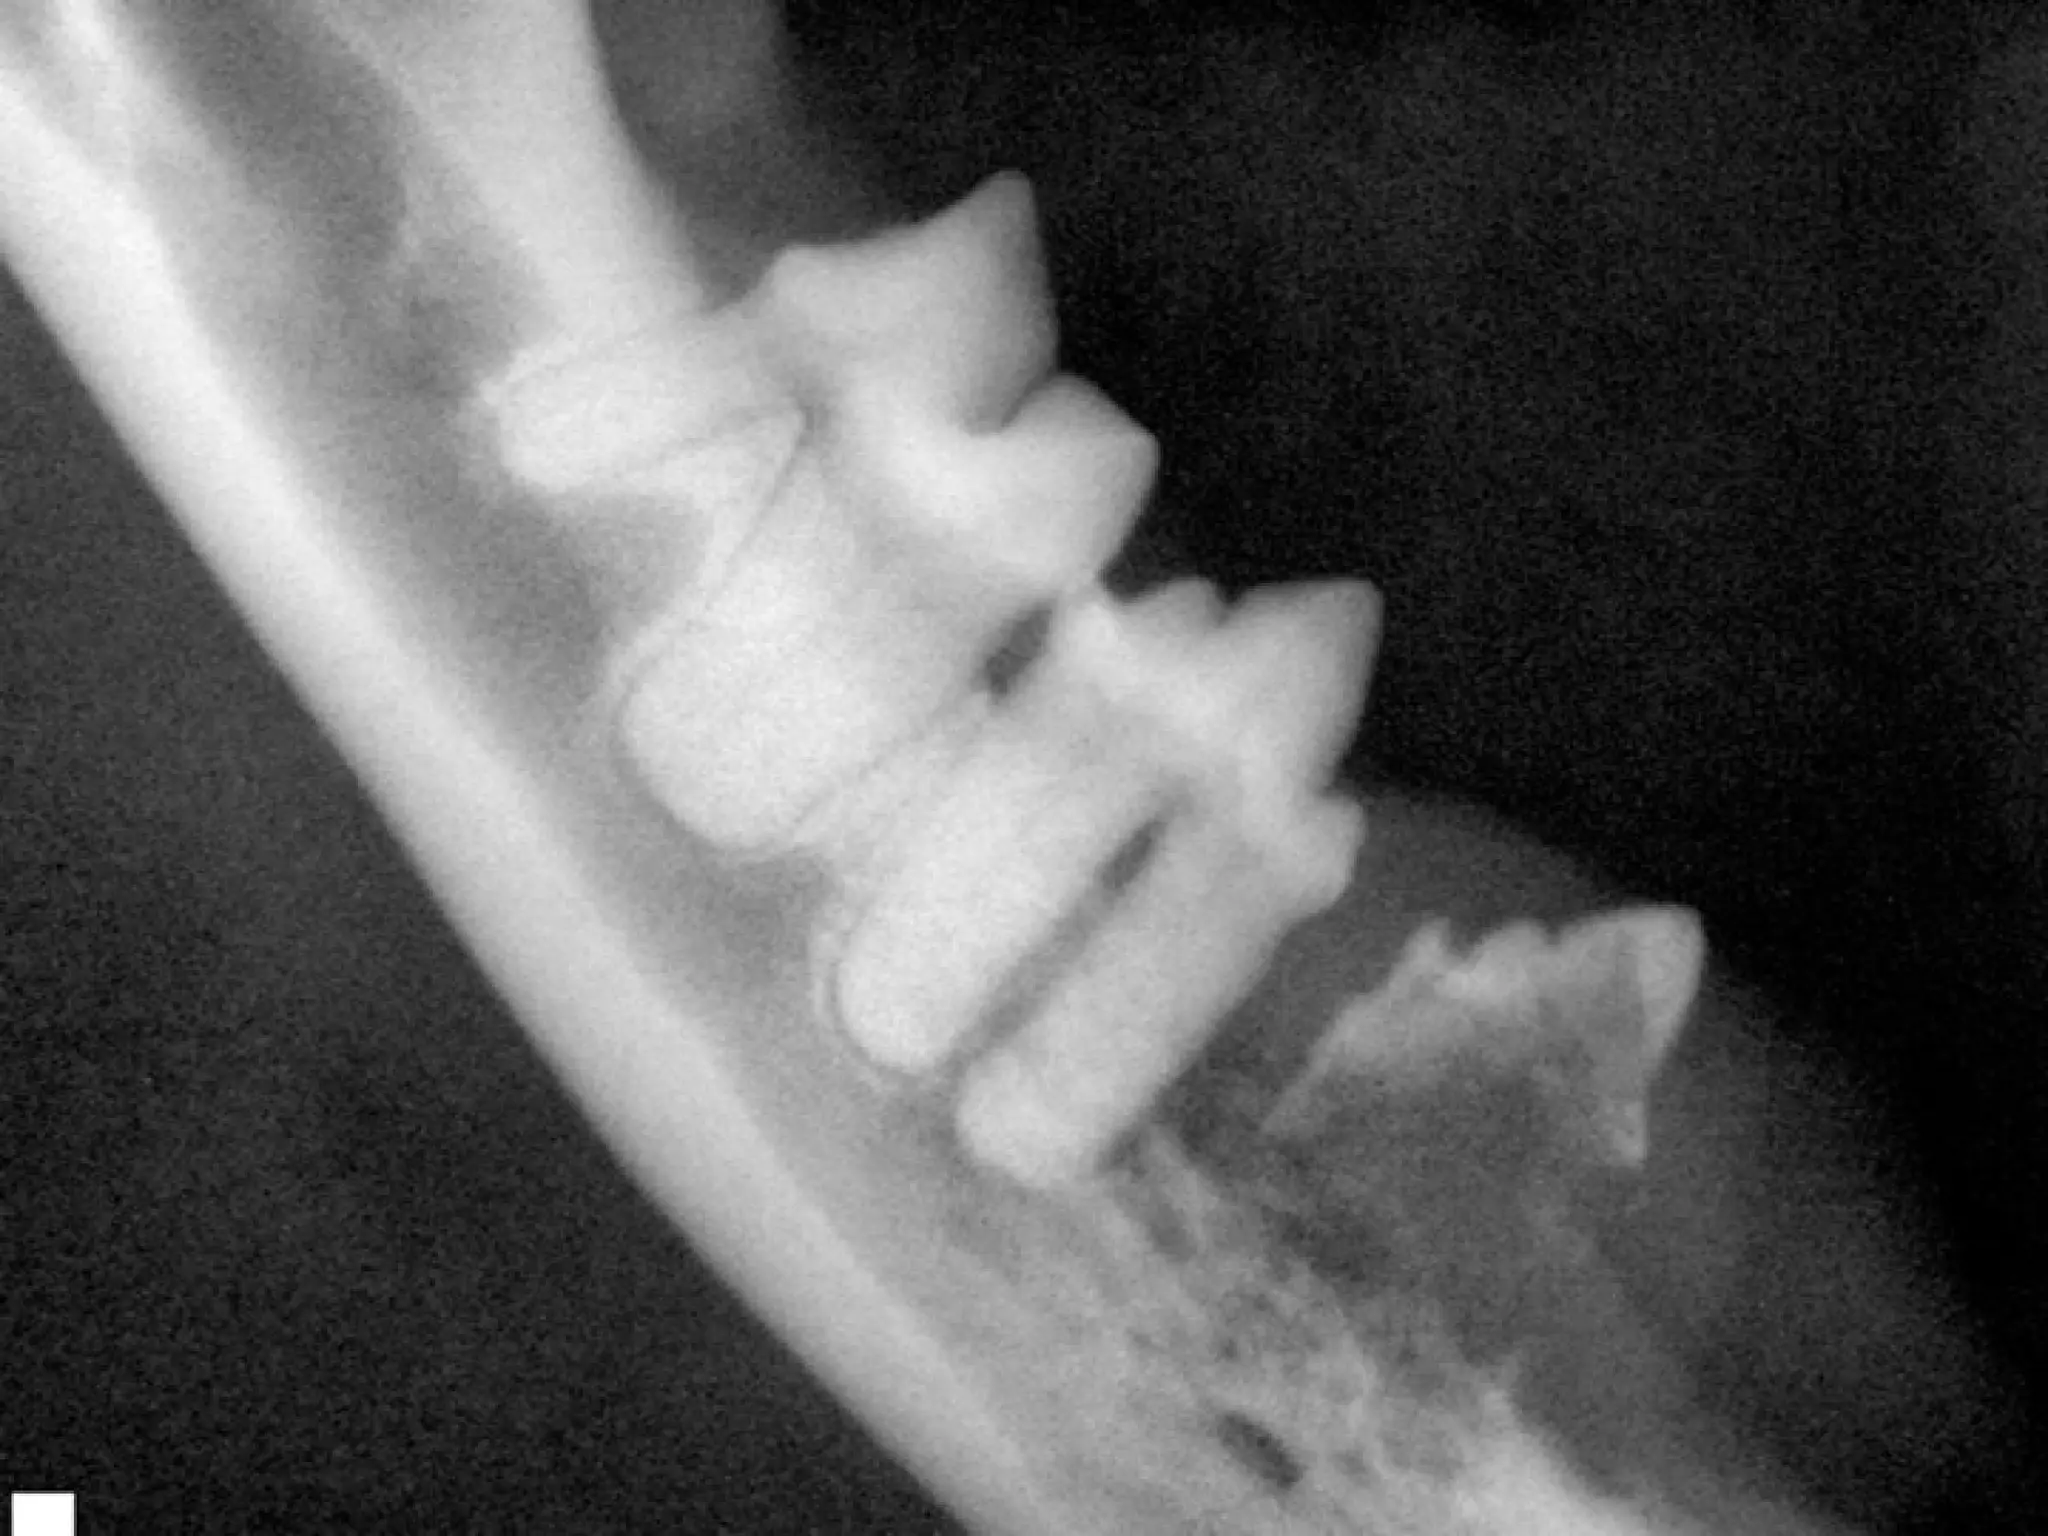

What disease is affecting the area

surrounding these teeth?

Is this the patient’s right or left

mandible?

What disease isaffecting the area surrounding these teeth? Is this the patient’s right or left mandible? 2